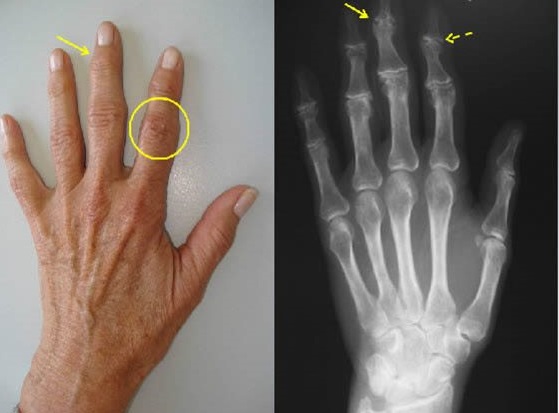

El diagnóstico de los nódulos de los dedos es principalmente clínico. La inspección visual, la palpación y la verificación de los arcos de movilidad de la articulación afectada generalmente son suficientes para hacer el diagnóstico.

Se puede solicitar una Rx, donde se puede evidenciar daño de la articulación, formación de osteofitos, disminución del espacio articular o luxaxión de las falanges. Estos cambios se conocen como artropatía y ayudan a identificar que tan avanzado está el problema y saber el tratamiento apropiado.